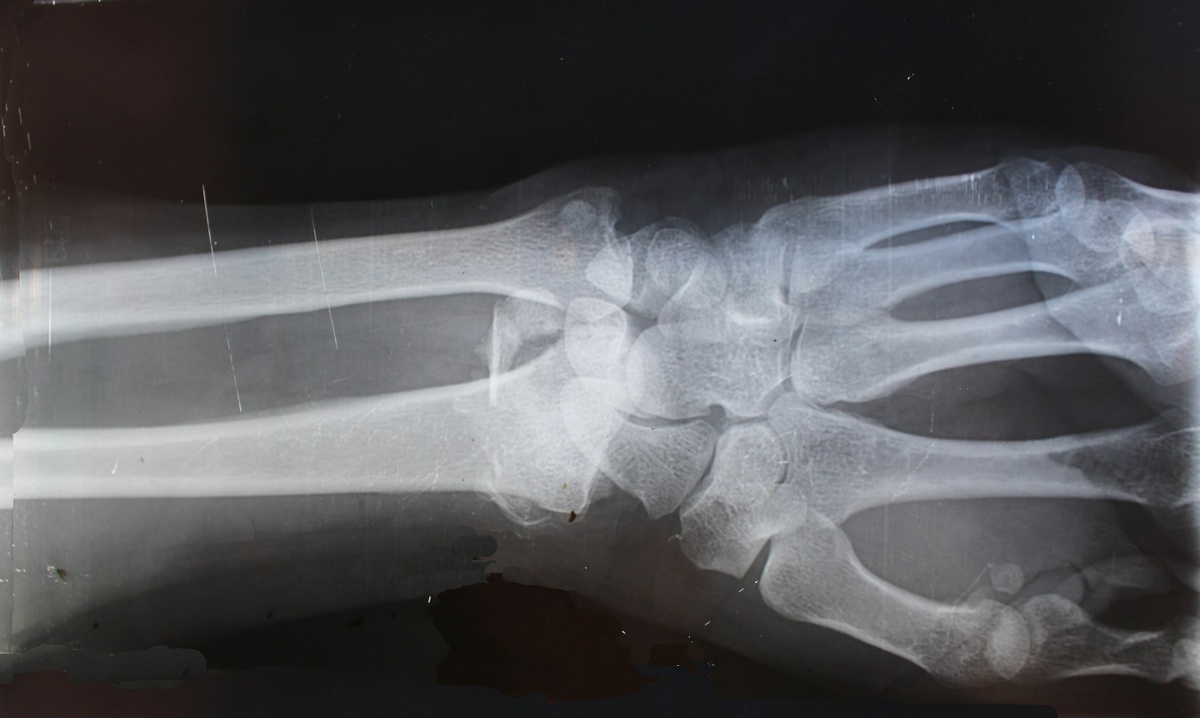

Только когда я попала на прием к хорошему ревматологу, которая сразу же отправила меня на рентген рук (сильно болели руки) и другие обследования диагноз подтвердился.